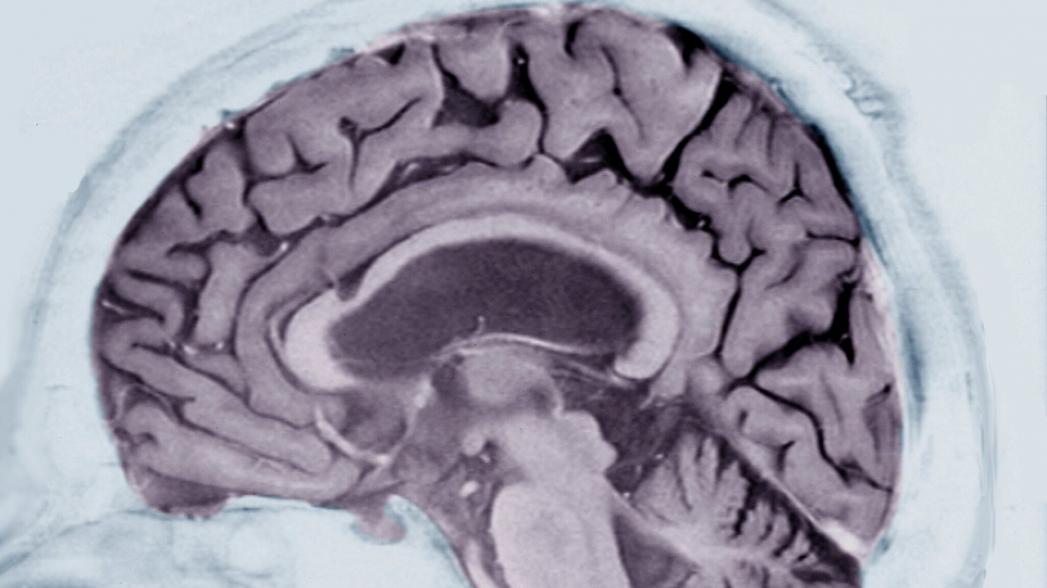

Новый алгоритм искусственного интеллекта, созданный IBM, может помочь врачам диагностировать или предсказывать наступление болезни Альцгеймера - за годы до появления симптомов.

Алгоритм рассматривает данные неврологического исследования, в котором приняли участие 270 человек, которым, помимо прочего, было предложено наглядно описать то, что происходило на простой картинке несколько раз в течение нескольких лет. Основываясь только на этих образцах, алгоритм научился распознавать такие закономерности, как все более повторяющиеся фразы, опечатки или недостающие слова, как признаки нейродегенеративного заболевания.